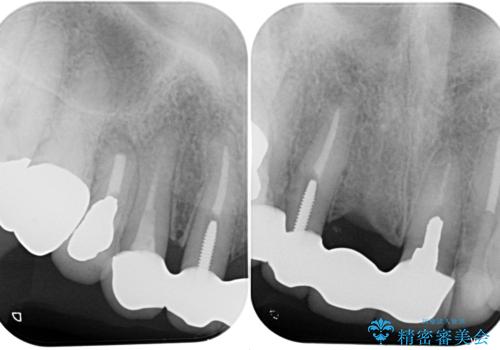

問題の歯は、歯根まで破折している状態で、抜歯が必要と判断されました。

ところが、土台となる歯は、十分な維持力が得られないほど歯ぐきの中に埋もれており、歯ぐきも腫れやすい状況でした。

まずは土台の歯を引っぱり出し、外科処置により歯肉の状態を十分に整えた上で、オールセラミッククラウンにて補綴することとしました。

元々の土台は歯肉の中に埋もれており、歯肉が著しく腫れている状態だったため、歯を引っぱり出すこととしました。引っぱる期間は2ヶ月ほどで済み、その後歯周外科処置を行ったことで、土台周りの歯肉は腫脹のない健全な状態へと改善されました。